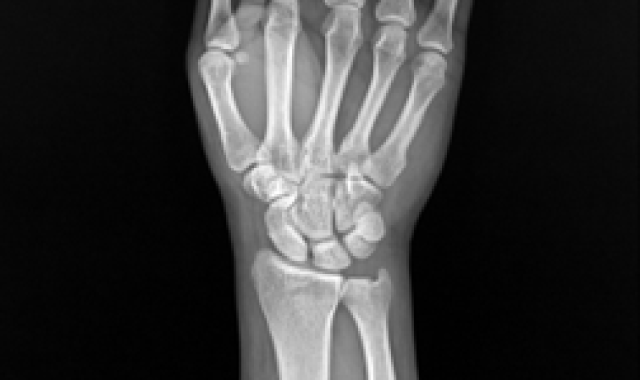

주상월상인대파열 진단법

X-ray 진단으로 보이지 않을 경우

→ 초음파, MRI 영상 검사

힘주지 않았을 때 우측

힘주지 않았을 때 좌측